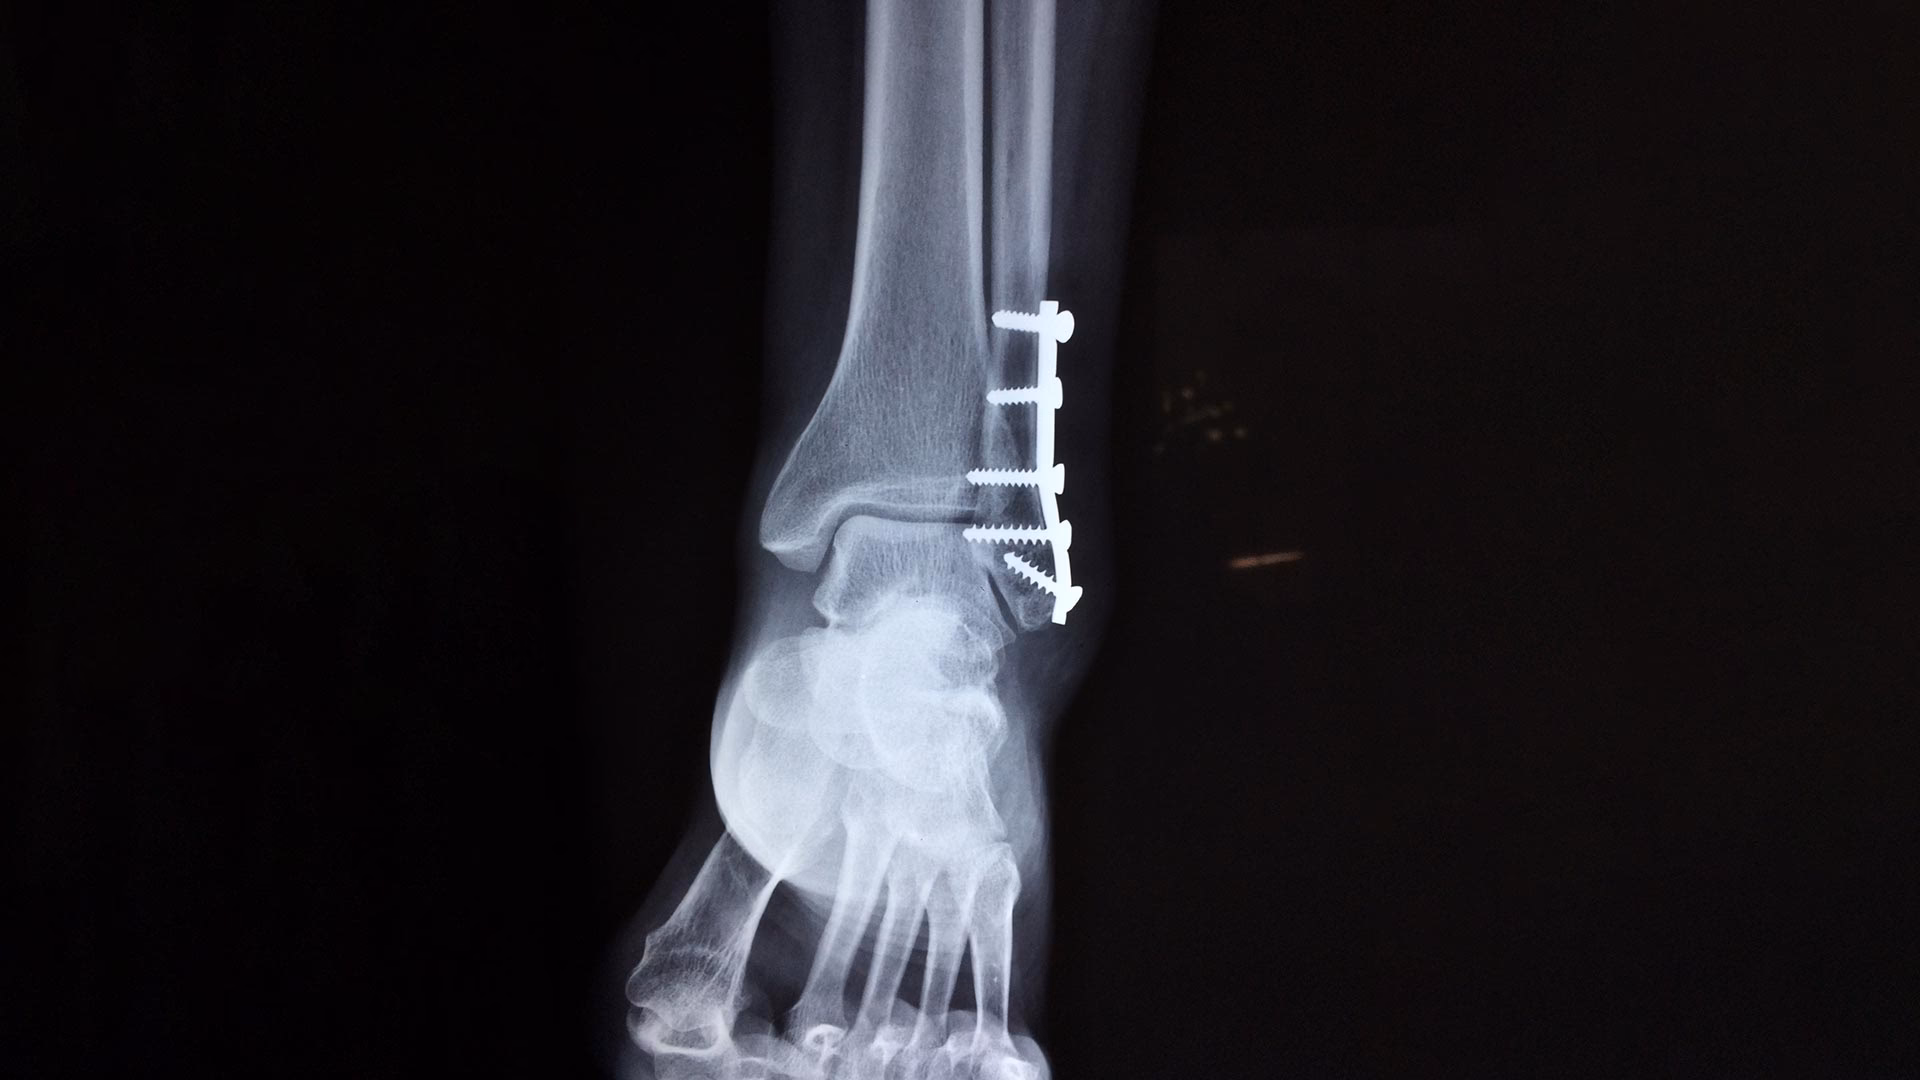

Operativ Behandling (Osteosyntese)

Ved komplicerede brud – for eksempel åbne brud, brud med mange fragmenter eller brud, hvor knogleenderne er meget forskudte – er en operation ofte nødvendig. Her vil kirurgen samle knoglestykkerne og fiksere dem internt med materialer som skruer, plader, søm eller wirer. Fordelen ved en operation er, at den skaber en meget stabil fiksation, som ofte tillader tidlig mobilisering. Dette er især livsvigtigt for ældre patienter med f.eks. en hoftenær fraktur, da langvarigt sengeleje kan føre til alvorlige komplikationer som lungebetændelse. Metalimplantaterne fjernes i nogle tilfælde efter 6-24 måneder, men hos ældre patienter efterlades de ofte permanent.